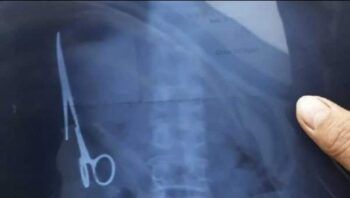

Un equipo médico de Bangladesh logró extraer esta semana con éxito una tijera quirúrgica del abdomen de una mujer, donde había permanecido durante los últimos 20 años después de una negligencia médica en una cirugía anterior. Bachena Khatun, de 55 años, fue operada este lunes en el hospital de Chuadanga Sadarun de Bangladesh y «se encuentra […]